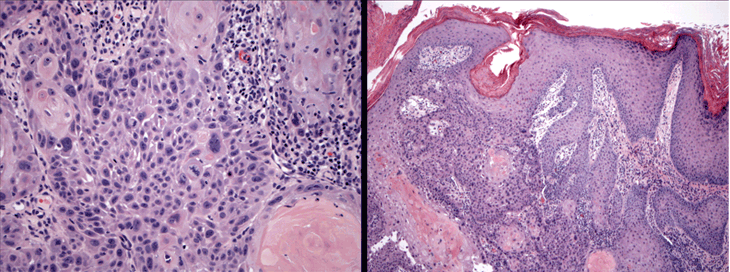

Estendem-se além da membrana basal, penetram na derme e podem invadir estruturas mais profundas. Os ceratinócitos atípicos têm núcleos hipercromáticos grandes e variáveis, e elementos mitóticos são observados. Existem graus variáveis de diferenciação, e CCEs indiferenciados e extremamente agressivos podem se manifestar como tumores de células fusiformes. A elastose solar é geralmente observada na derme superficial, refletindo a extensão da exposição crônica aos raios UV.[Figure caption and citation for the preceding image starts]: Histologia da biópsia mostrando carcinoma de células escamosas (CCE) invasivo com atipia de ceratinócitos envolvendo todas as camadas da epiderme e ilhas brotando na dermeDo acervo particular de Dr. Nwaneshiudu e Dr. Soltani [Citation ends].

[Figure caption and citation for the preceding image starts]: Biópsia mostrando a histologia característica de um carcinoma de células escamosas (CCE) invasivo com atipia de ceratinócitos envolvendo todas as camadas da epiderme e ilhas brotando na derme. A ampliação maior (esquerda) destaca a atipia celularDo acervo particular de Dr. Nwaneshiudu e Dr. Soltani [Citation ends].